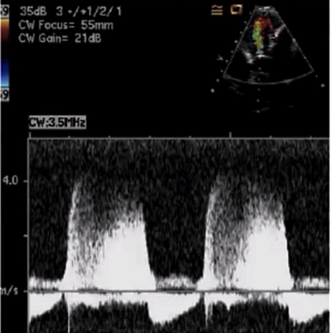

- Transthoracic versus transesophageal echocardiographic and Doppler images in a patient with severe paravalvular MR.

严重瓣周 MR 患者的经胸超声心动图和经食管超声心动图和多普勒图像。 - Shadowing on TTE of the left atrium (arrows) masked significantly the regurgitant jet by color Doppler (single white arrow).

左心房 TTE 上的阴影(箭头)通过彩色多普勒(单白色箭头)显着掩盖了反流束。 - The extent of valvular dehiscence is shown by the green arrow on TEE as well as the severity of regurgitation by color Doppler.

瓣膜裂开的程度由 TEE 上的绿色箭头表示,反流的严重程度由彩色多普勒表示。